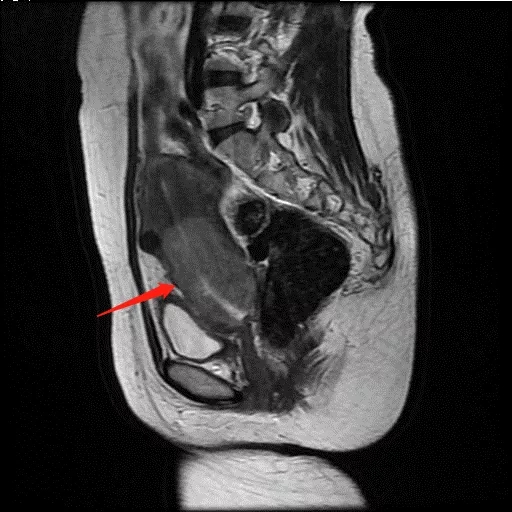

▲通过盆腔MRI发现子宫颈-子宫体中下段占位,考虑诊断宫颈癌